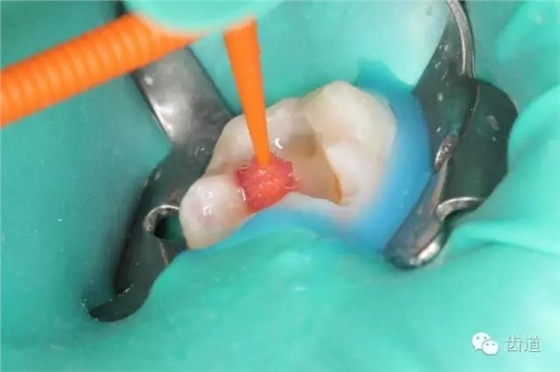

2. 超聲清理去除暫時(shí)充填物

3. 試戴嵌體就位良好

4. 30%磷酸算蝕牙體粘接面

5. 涂布Bisco All Bond 粘結(jié)劑 20s

6. 光照固化20s

7. 氫氟酸酸蝕修復(fù)體粘接面15s

8. Bisco Dual link 瓷處理劑涂布修復(fù)體粘接面

9. Bisco Dual link 樹(shù)脂水門汀 完成嵌體粘固

10. 術(shù)后即刻口內(nèi)照片